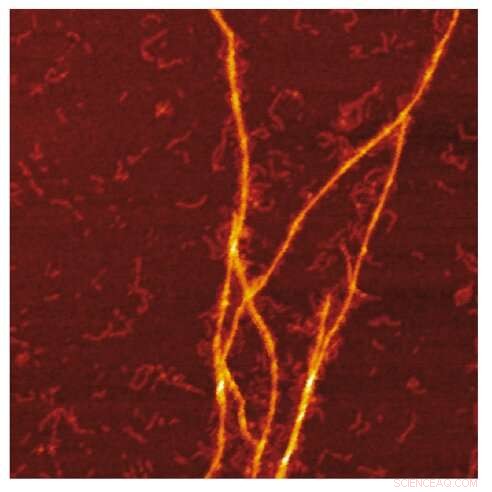

AFM image of the amyloid templating of S100A9 fibrils on the surface of Aβ fibrils. Credit: Jonathan Pansieri

Combination of mass and charge distributions of amyloids together with reconstruction of the differences between them and detailed microscopy reveals that co-aggregation involves templating of S100A9 fibrils on the surface of Aβ42 amyloids. Kinetic analysis further corroborates that the surfaces available for the Aβ42 secondary nucleation are diminished due to coating by S100A9 amyloids, while the binding of S100A9 to Aβ42 fibrils is validated by a microfuidic assay.